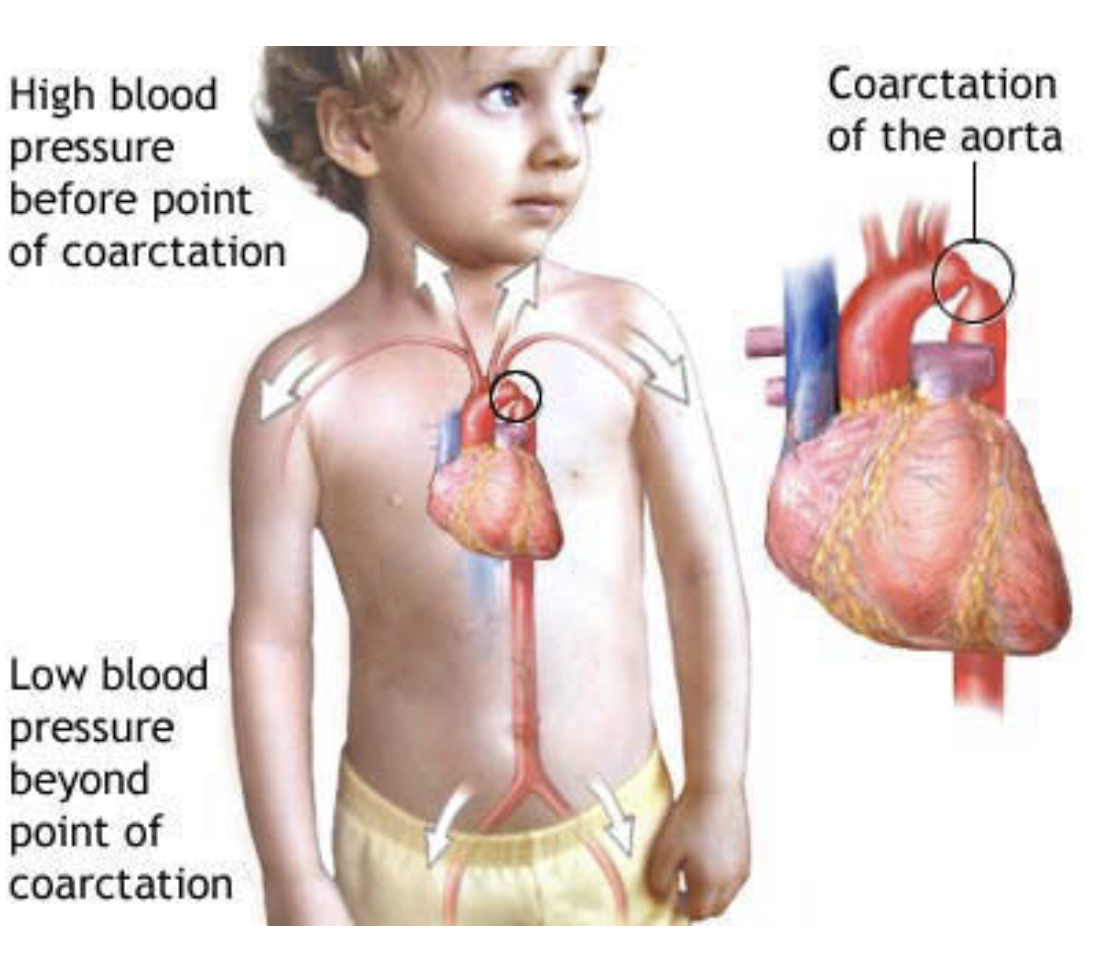

Clinical drop — coarctation of the aorta

A congenital abnormality where the aortic lumen is constricted just distal to the origin of the left subclavian artery

At this point the aorta becomes significantly narrowed & the blood supply to the abdomen & lower limbs is diminished

Collateral vessels may develop around the chest wall & abdomen to supply the lower body

These intercostal veins which form a bypass to supply the descending thoracic aorta may lead to erosions of the inferior margins of the ribs — can be observed in radiographs as inferior rib notching

This coarctation also affects the heart, which has to pump the blood at a higher pressure to maintain peripheral perfusion — may produce cardiac failure